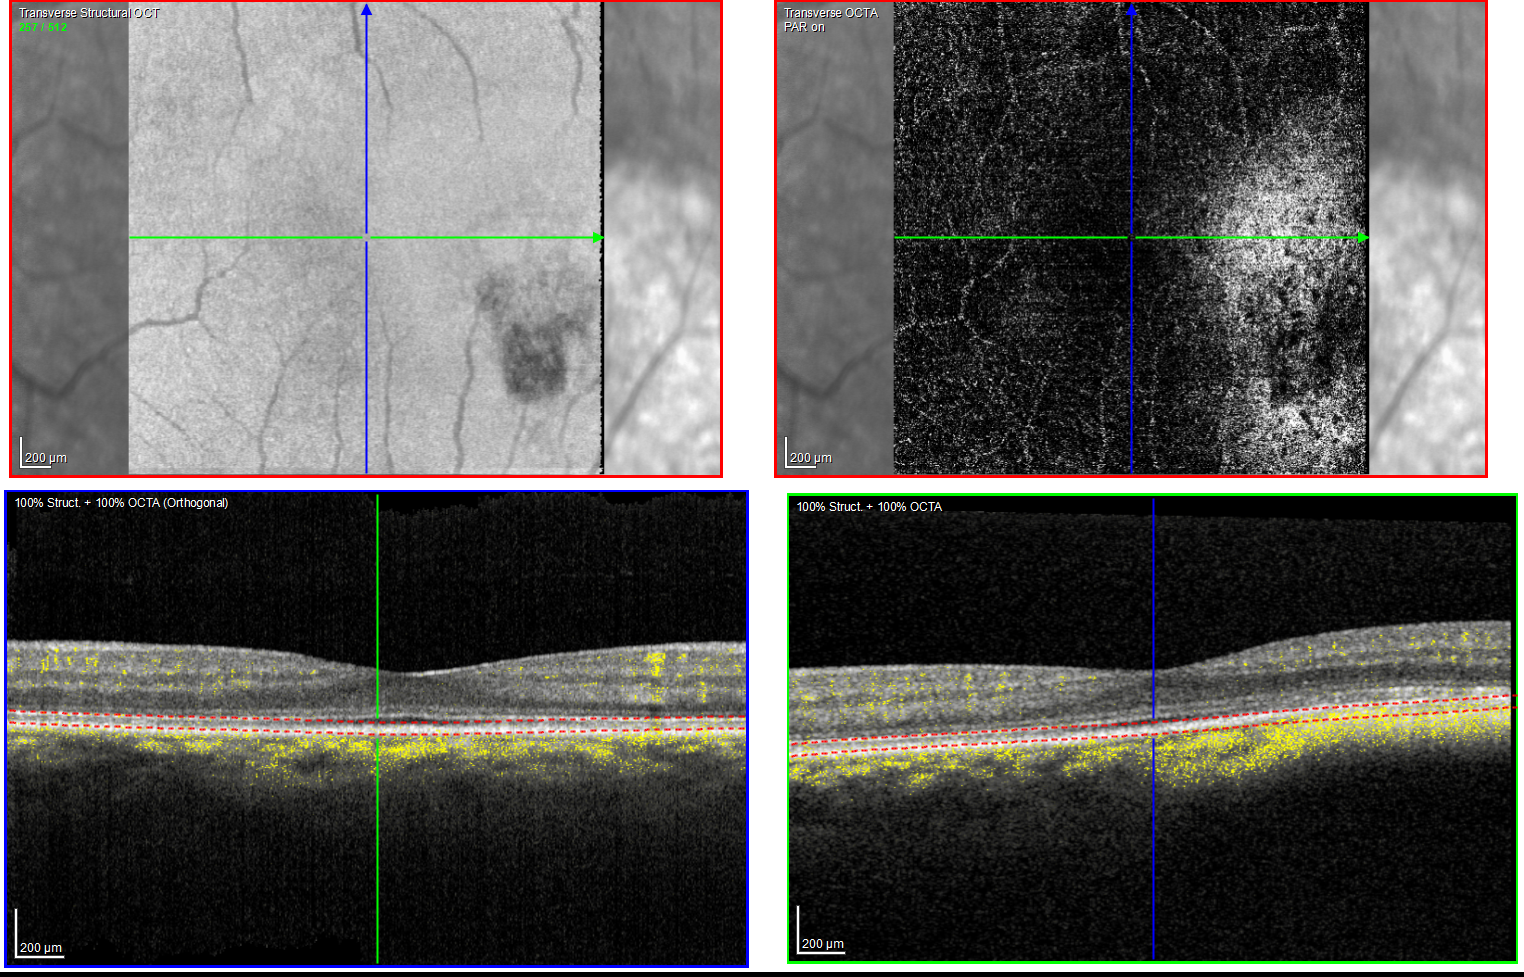

The patient had a small, flat pigmented lesion in the left macula. Fundus autofluorescence showed punctate hyperautofluorescence. Optical coherence tomography (OCT) demonstrated a minimally elevated choroidal mass that had replaced the normal choroidal vasculature. There was a serous pigment epithelial detachment without subretinal fluid or macular edema. OCT angiography did not reveal a choroidal neovascular membrane (CNVM). Fluorescein angiography showed mottled hyperfluorescence in both early and late phases without evidence of leakage.

These findings are most consistent with a choroidal nevus associated with a pigment epithelial detachment. Although CNVMs can arise over nevi, no evidence of CNVM activity was detected in this case. An occult CNVM remains a possibility, and the patient is being monitored accordingly. The punctate hyperautofluorescence raises the possibility of a small melanoma, and the presence of overlying subretinal fluid increases this concern. However, there has been no change in the size or characteristics of the lesion over the past year.